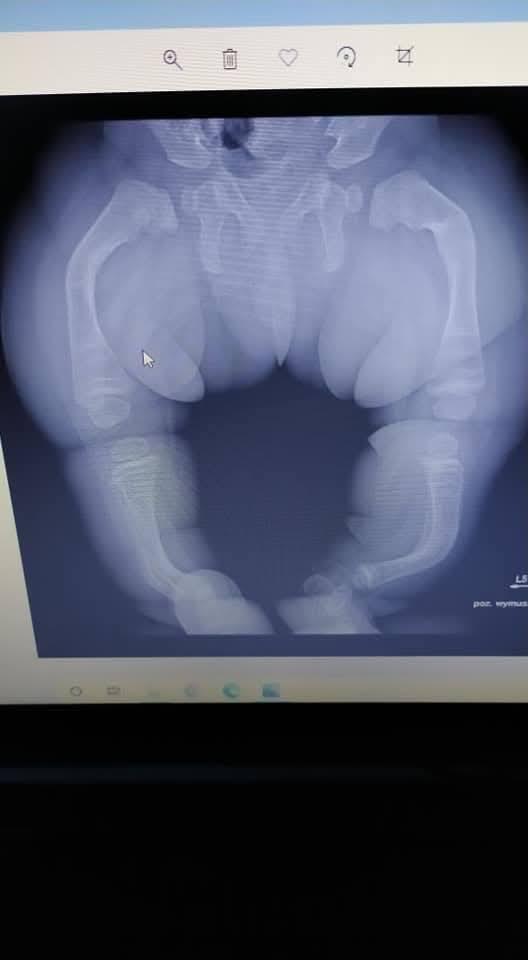

Madzia choruje na wrodzoną łamliwość kości typu III (osteogenesis imperfecta) – rzadką, genetyczną chorobę tkanki łącznej, która powoduje skrajną kruchość kości. Złamań doznała już w życiu płodowym, a jej organizm nie produkuje kolagenu. Choroba jest nieuleczalna, a leczenie ma charakter objawowy i obejmuje stałą rehabilitację, liczne operacje, stabilizację kości oraz specjalistyczną farmakoterapię. Dziewczynka ma za sobą już kilka poważnych zabiegów oraz kilkanaście podań leków wzmacniających kości. Przed nią kolejne operacje i intensywna fizjoterapia, bez której trudno byłoby myśleć o większej samodzielności.